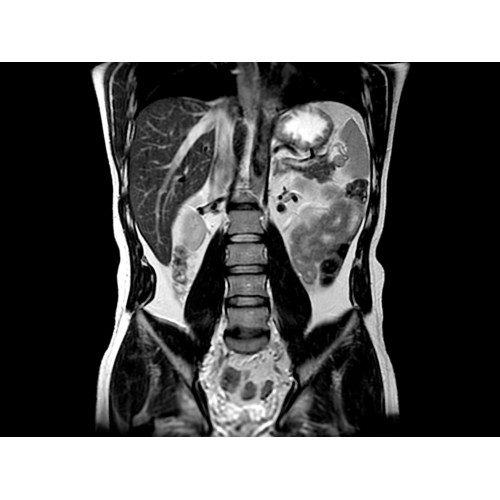

• Комплексная оценка печени — первая в отрасли ИП MR-Touch открывает новые возможности диагностики благодаря способности определять различия в жесткости тканей.

МР-эластография: неинвазивная методика комплектной оценки печени

Пациентам с такими хроническими заболеваниями печени, как фиброз и цирроз, часто требуется регулярное наблюдение гастроэнтеролога. Это может потребовать проведения инвазивных процедур, которые не всегда позволяют получить полную информацию о состоянии печени.

Новая ИП MR-Touch, разработанная компанией GE совместно с клиникой Майо, основана на исследовании печени с помощью акустических волн, в ходе которого выявляются различия в жесткости тканей. Результатом исследования является эластограмма, полное изображение печени. По таким эластограммам радиологи и гастроэнтерологи могут периодически контролировать состояние пациента и принимать информированные решения о терапии. Более того, данная методика открывает новые возможности и позволяет оказывать инновационные услуги имеющимся пациентам и привлекать новых клиентов.